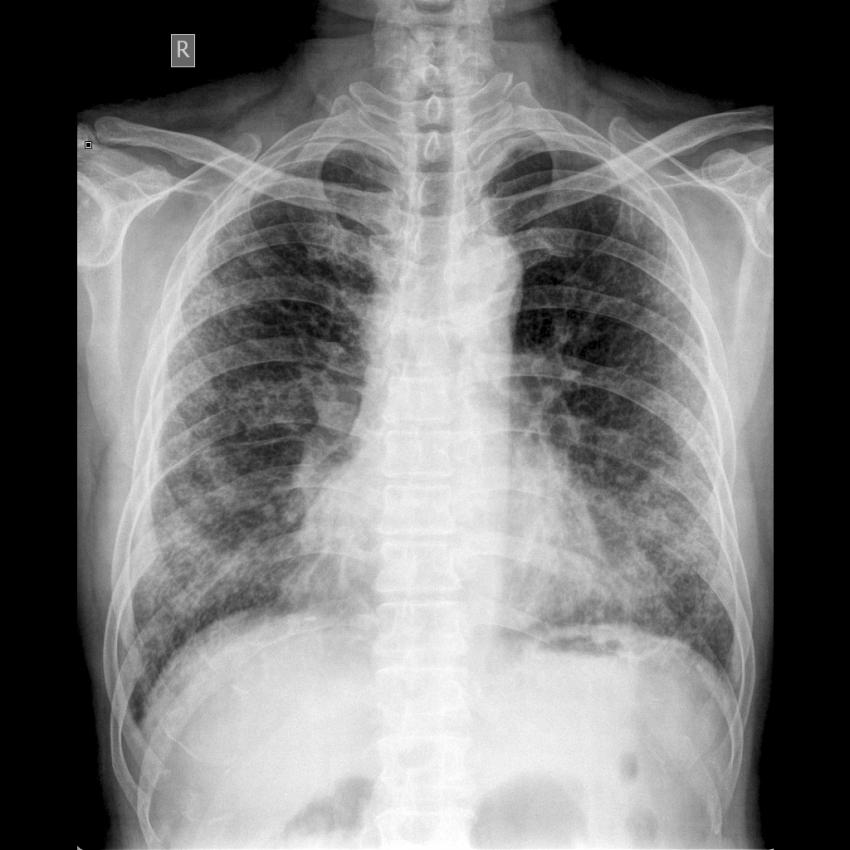

中医科《胸片》学习课件

由于《胸片》学习课件内存过大,无法上传到网上。如有需要者,请到中医科拷贝。

附:课件样本。

1、风心病:

2、双肺陈旧性肺结核:

3、双肺间质纤维化: